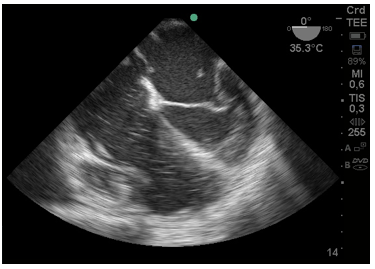

En la Figura 3:, se observa trombo cruzando por el foramen oval del tabique interauricular y trombosis en aurícula izquierda (AI).

Figura 3: Imagen de 4 cámaras donde se ve trombo en aurícula izquierda y otro pasando desde la aurícula derecha por el foramen oval. Cavidades derechas aumentadas de tamaño.

En la Figura 4:, se observa un trombo a nivel de la válvula mitral en condiciones de migrar hacia el ventrículo Izquierdo.